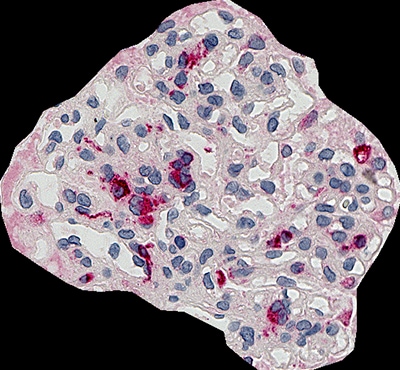

Ein Beispiel für die Analyse des Flächenverhältnisses des CD68 im Glomerulus ist unten dargestellt. Nachdem die HE-Färbung durchgeführt wurde, wurde eine Nierenbiopsie von oben betrachtet aufgenommen. Normalerweise ist es schwierig, das Bild zu fokussieren, wenn die Probe dick ist, aber die Z-Stapel-Bilderfassung ermöglicht, dass das gesamte Bild scharf abgebildet wird.

Glomerulus-Flächenverhältnis: 4,3%